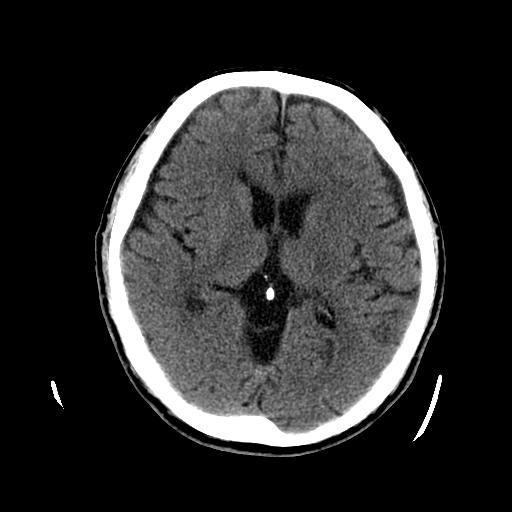

患者入科后,对患者进行详细的检查,患者跌倒在地不能起来需要考虑是否是脑卒中,所以就对患者进行了神经系统查体,患者神志清楚,表情呆滞,不能对答,但是患者口角无歪斜,双上肢及左下肢可见活动,右下肢未见明显活动,病理征也是阴性,所以考虑脑卒中的依据不充分。这种情况需要考虑患者是否因为局部病变引起,比如右髋关节是否有骨折,因为老年人很容易在发生跌倒的情况下出现骨折,加之该患者有严重的痴呆,对疼痛不敏感,所以对患者右下肢进行了查看,髋部无皮下淤血,按压可见患者用手阻挡并有痛苦的表情,在看看右下肢有缩短外旋的情况,所以就高度怀疑存在骨折,安排患者进行了骨盆CT检查,提示右侧股骨颈骨折,所以疾病诊断明确了。

该患者由于突发跌倒后出现右下肢股骨颈骨折,跌倒在厕所不能自行起来,出现这种情况也不除外脑血管意外,所以在临床判断时必须严谨,避免误诊,需要早期识别才能进行正确的处理。对于老年患者由于年龄因素、骨密度减弱,骨质变得松脆,轻微外伤就可能引起骨折,所以平时老年患者需要常规补钙抗骨质疏松。特别是该患者有严重的痴呆,对日常生活缺乏灵活性和协调性,日常行走时很容易发生跌倒,在厕所这些地板容易滑倒的地方需要做好安全防护,比如安置防滑垫,扶手,或者给患者使用大便座椅。该患者在日常生活中家人需要多关注,重视一些容易引起意外的情况发生,比如水、电、气的使用,由于患者在使用这些后常常忘记关闭,导致发生意外。